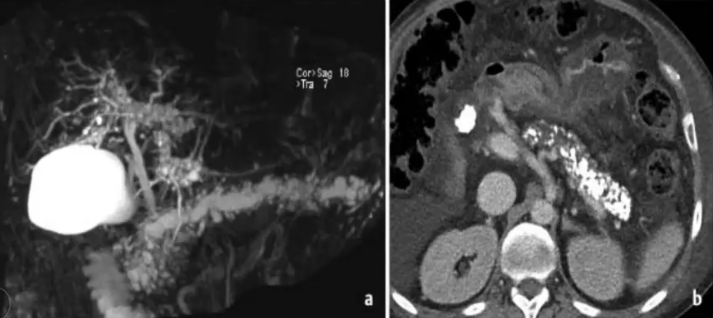

❖ 下图:胆管周围囊肿,ERCP造影无左肝胆管扩张,反而有狭窄表现

❖ 胰腺结石伴慢性胰腺炎伴有胆管周围囊肿